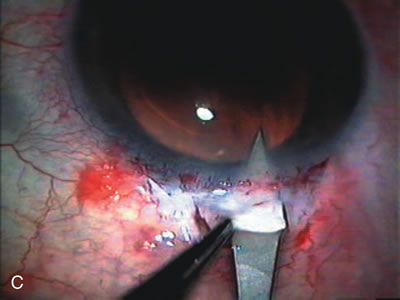

Fig. 1. The anatomic advantage of small incision cataract surgery for the glaucoma patient. A. Long-term bleb function with a large cataract incision is difficult to achieve with either ECCE-trabeculectomy or trabeculectomy followed later by ECCE. This bleb failed to form sufficiently when combined with large incision ECCE. The inflammation, bleeding, and long-term wound healing with stimulation of fibroblasts associated with this technique are more likely to cause bleb failure. In addition, the increased iris manipulation necessary to deliver the nucleus and subsequent iris repair adds to the long-term breakdown of the blood aqueous barrier. B and C. Two-site phacotrabeculectomy has the advantage of small incision cataract surgery combined with separate site trabeculectomy. The incision size is one third the size of the standard ECCE. The inflammation is less severe, and cataract wound healing is confined to the temporal area. Visual rehabilitation with phacoemulsification and foldable IOL is much faster. Phacoemulsification allows successful lens extraction even in the unfriendly environment of a smaller pupil compared with ECCE. The trabeculectomy is performed in an entirely different site, well away from the wound healing associated with temporal phacoemulsification. The likelihood of this filter functioning long-term is greater than with ECCE-trabeculectomy. D. The surgeon also has the option of single-site phacotrabeculectomy with foldable IOL. Both the lens extraction and trabeculectomy are performed through one small 3.5-mm limbal incision.